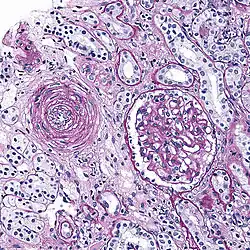

Hyaline arteriolosclerosis

Also arterial hyalinosis and arteriolar hyalinosis refers to thickening of the walls of arterioles by the deposits that appear as homogeneous pink hyaline material in routine staining.[3] It is a type of arteriolosclerosis, which refers to thickening of the arteriolar wall and is part of the aging process.[4]

Hyperplastic arteriolosclerosis

This is a type of arteriolosclerosis involving a narrowed lumen.[4] The term "onion-skin" is sometimes used to describe this form of blood vessel[14] with thickened concentric smooth muscle cell layer and thickened, duplicated basement membrane. In malignant hypertension these hyperplastic changes are often accompanied by fibrinoid necrosis of the arterial intima and media. These changes are most prominent in the kidney and can lead to ischemia and acute kidney failure. In the brain, a small cavity called a lacune is an ischemic cavity that can arise due to brain necrosis, due to arteriolosclerosis.[15][16]